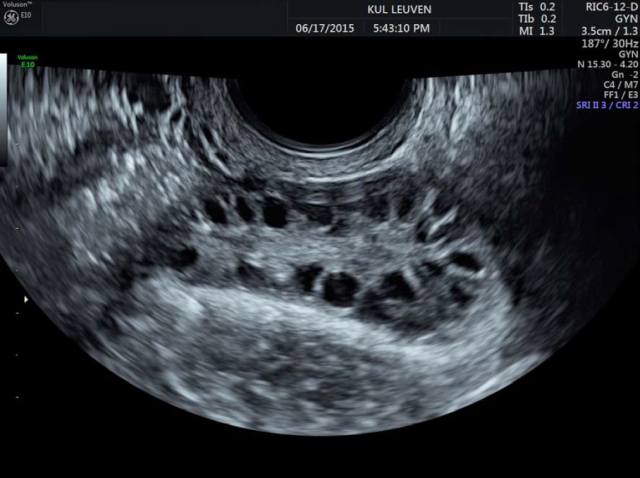

多囊卵巢症患者的卵巢在超音波下通常可見多顆小濾泡,通常定義為單側卵巢超過10個直徑約2-9毫米的小濾泡,這是符合國際鹿特丹共識中多囊卵巢形態的標準之一。 -

隨著超音波技術的進步,尤其是三維(3D)及四維(4D)超音波,可以更精細地評估卵巢的體積及細部解剖結構,並透過能量多普勒(Doppler)技術評估卵巢血流狀況,這些指標與雄激素濃度及高雄性激素血症有顯著相關,有助於多囊卵巢症的診斷與鑑別。 -